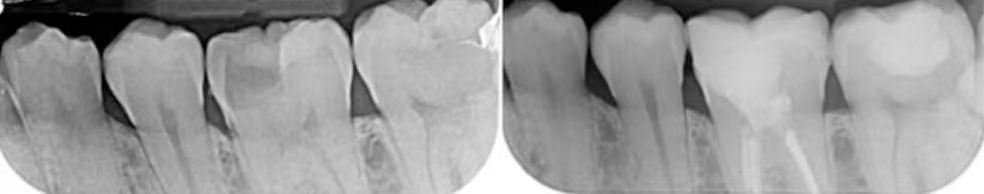

历史上是错误的,因为早在复合时代之前,DME就通过银汞合金和铸造金属在牙科中被广泛使用,即使在今天,作者仍然在选定的案例中使用(图1和图2)。技术上被误解了,因为DME不仅适合粘接间接修复,而且主要用于直接修复(两阶段方法)和常规冠粘接。

图1:龈下较深,游离龈缘下4mm,采用电刀进行DMA。封闭是通过特氟龙实现的。非解剖(无基质)银汞合金重建内部,进行无肩台预备,用来消除自由手DME带来的悬突,并产生箍效应。

图2:龈下很深,采用电切的方法进行边缘采集。封闭是使用特氟龙。非解剖(无基质)银汞合金内部重建,进行了E-max全覆盖。